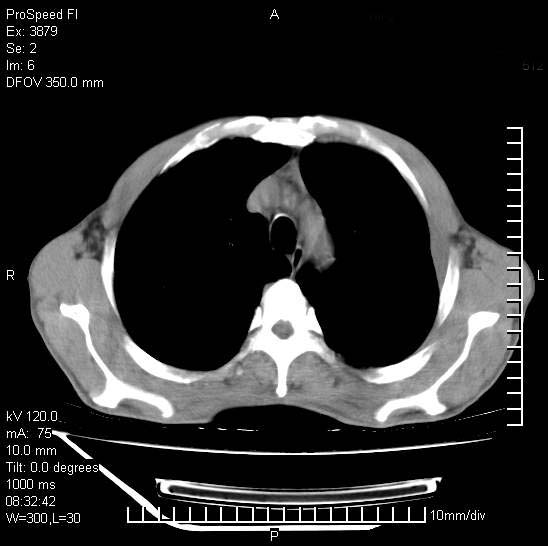

以下是引用37度在2008-6-6 11:20:00的发言:[br]1.包裹性积液,多考虑结核性;[br]2.穿刺术后改变。